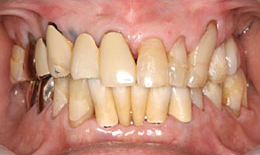

インプラント症例(8)72歳 男性

治療前